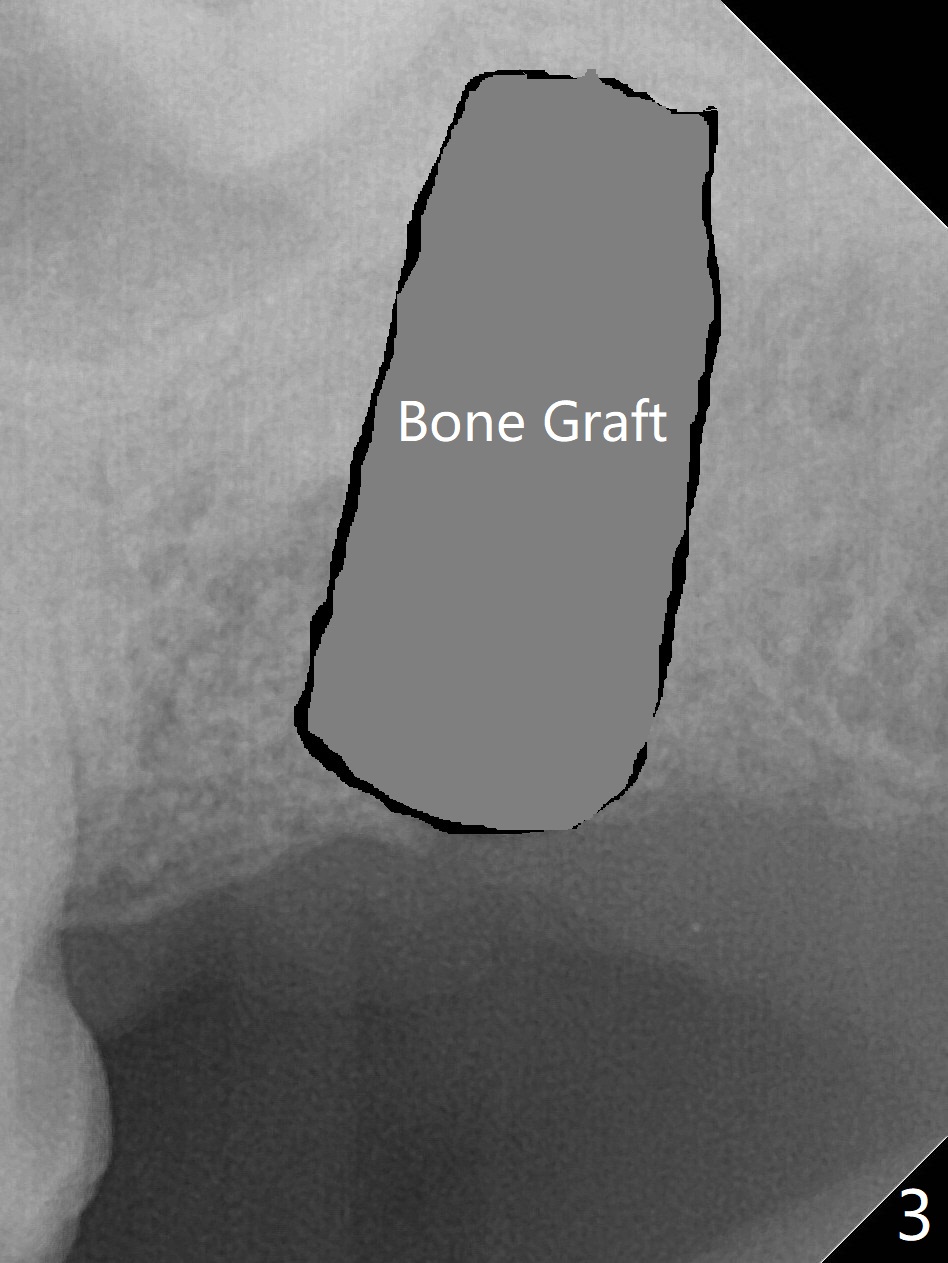

59岁男一年前因15号牙植牙周围炎去除牙冠和基台,植骨(图一:*(其实是第二次为周围炎植骨)),缝合。之后局部疼痛没有完全消失,准备再次手术(切开),如果螺纹暴露少,再次植骨。否则拔除植体(图二:黑色,手术探查的确不能挽救植体),之后有两个选择植骨(图三:灰色)或者即刻再次种植。由于原来植体比较粗(骨水平;6x12毫米),利用6(内径)/7(外径)毫米trephine drill和牙挺除去植体,留下相当大缺损(图二),植骨后(图三),位于缺损中间的骨粉(图四:棕色)可能因血供(红箭头)不足而愈合不佳。因此即刻重新种植显得有优势(图五(软组织水平植体,螺纹在自身骨(native bone)下)),让身体不必太辛苦(成骨)。放置5x5毫米基台目的是为树脂敷料提供固定点,以防PRF膜和缝线不能挽留粘性骨粉(*)。术后一个月撤除树脂敷料,伤口愈合正常(图六)。准备一个月后,制作临时牙冠。术后4个月取出5x5毫米基台,准备放置6x5毫米基台(图七),下面软组织水平植体没有疼痛或者松动,螺纹被骨粉或者再生骨质覆盖(^)。